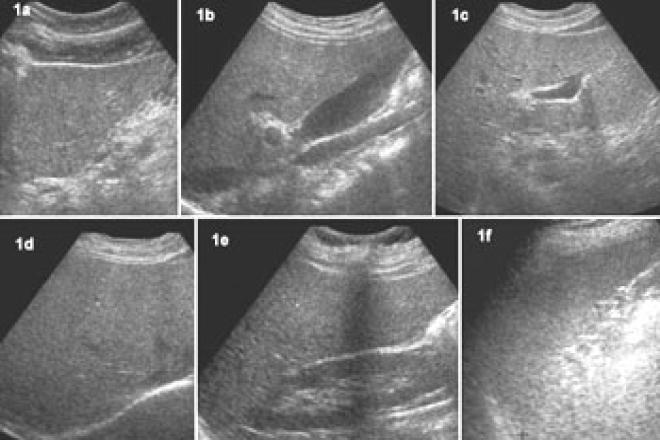

La ultrasonografía es una rama de la imagenología médica con ella realizamos diagnósticos tempranos que pueden cambiar el curso de una determinada patología, en la actualidad el uso del ecógrafo se vuelve cada vez más importante en el primer nivel de atención ya que la